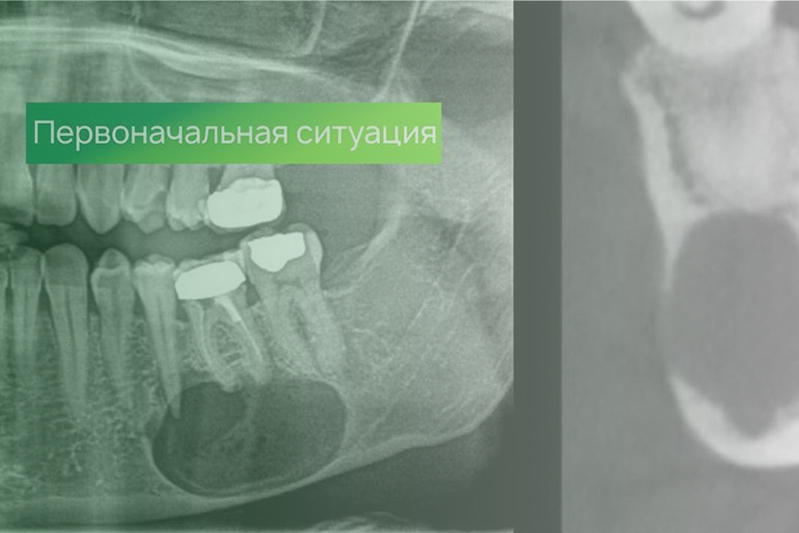

Клинический случай. Эндодонтия